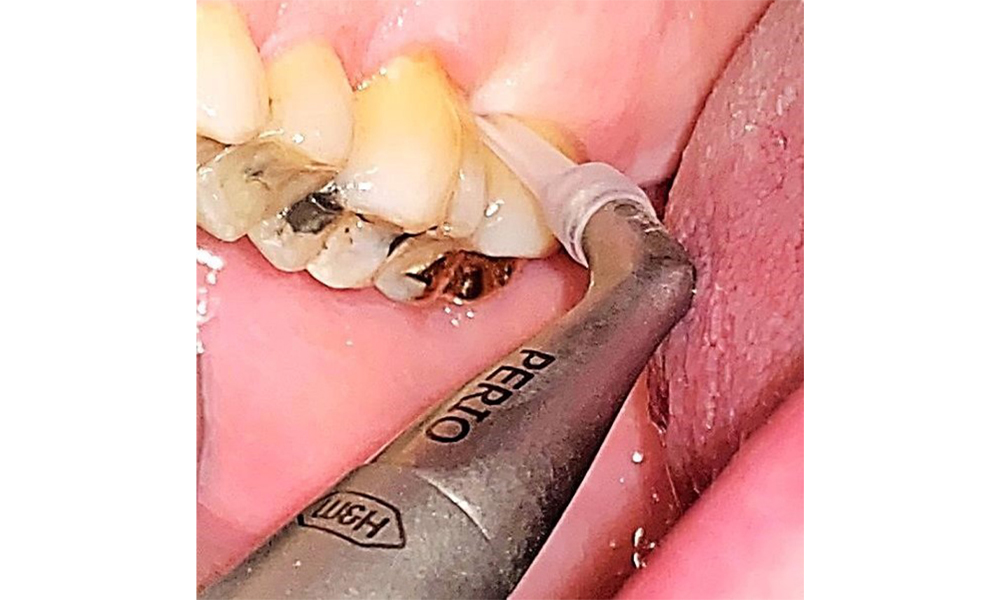

There are no limitations regarding the choice of instrumentation methods. Regular supragingival and subgingival instrumentation is essential to prevent disease progression due to the pre-existing periodontitis and high risk of recurrence. There are no limitations placed on the selection of instruments for mechanical biofilm removal from a general medical perspective, and removal should be performed as needed. Hard and mineralized plaque, such as calculus and concretions, should be removed using manual instruments or sonic/ultrasonic scalers (Fig. 9) (8, 9).